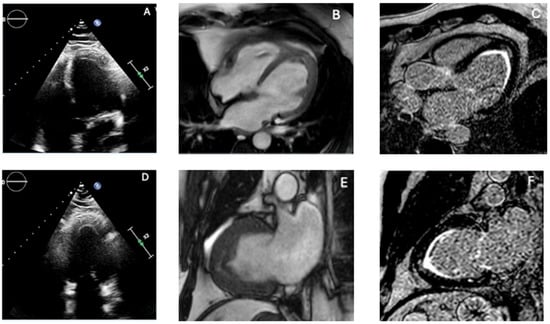

In addition to standardized lateral cephalometric radiographs, comprehensive assessment using dental cone-beam computed tomography (CBCT) and CT has become commonplace in the diagnosis and treatment of jaw deformities. Simulation based on cephalometr...